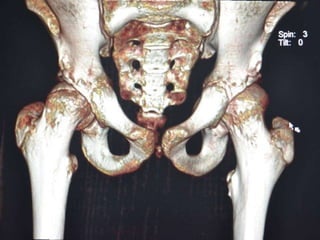

 CT SCAN-

Accurately measures extent of epiphyseal displacement & angulation.